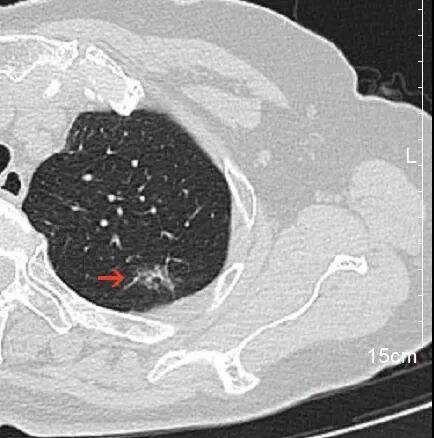

“吴主任,麻烦您给看看,老严是不是和我一样幸运!” 浙大二院解放路院区胸外科吴明主任医师的诊室内今天特别热闹,夏大伯带着他的钓友严大伯前来求医,期望朋友能和自己一样幸运。 事情要回溯到2个月前。年前夏大伯“阳”了一周后,依旧觉得浑身不得劲,来到浙大二院滨江院区做了胸部CT。 不查不知道,一查吓一跳。本来还只是“不得劲”的夏大伯,年三十看到自己的CT报告,当场就感觉四肢无力,呼吸都有些困难了。丰盛的年夜饭,在CT报告“肿瘤不除外”这几个字面前,也变得索然无味。 夏大伯是怎么都在家里待不住了,第二天一大早就再次来到了滨江院区,碰上了过年期间坐诊的胸外科吴明主任医师。 吴明仔细查看了夏大伯的CT,认为这个肺结节看着虽不能完全排除肿瘤,但炎症所致的概率更大。便劝夏大伯放宽心,回去口服抗生素治疗半个月,1个月后再复查胸部CT。 夏大伯“百度”了吴明医生的专家资料后,又听他这么说,悬着的心放下了一半。 待1个月后复查 悬着的另一半心更是彻底放下了 他的肺结节基本消失了 当得知自己的钓友也查出了肺结节,夏大伯二话不说就带着他来到了吴明医生的门诊。 吴明看了严大伯的CT片子,认为虽然他的肺结节中也有炎症成分,但是恶性的可能性也不低。果不其然,经过半个月的抗炎治疗,1个月后严大伯复查了胸部CT,肺结节虽然缩小了,但并未完全消失。 “是不是消炎药不够好?要不要再吃半个月?” “要不要挂盐水?” 严大伯和夏大伯明显还希望通过抗感染治疗,把肺结节治好。 吴明医生告诉他们说,肺结节之间是不同的,需要结合多方面的因素去综合判断。严大伯的这个肺结节恶性的几率还是很高的。 术后,病理果然提示: